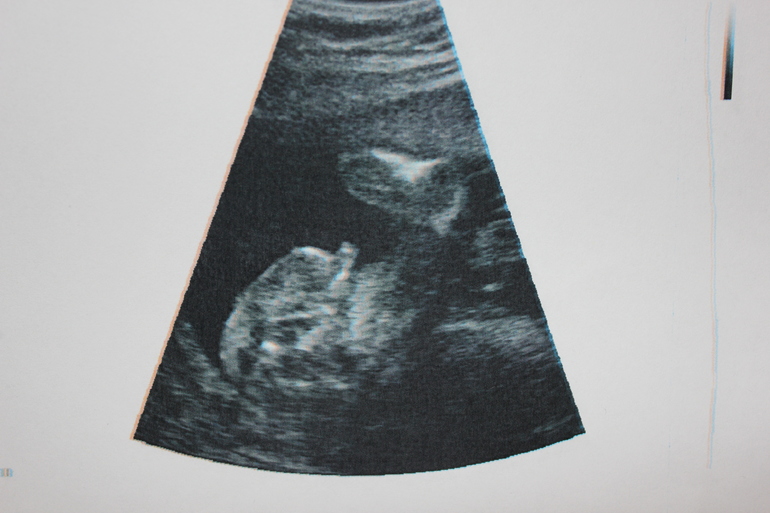

Итак, в 21 неделю +1 день мы имеем:

Рост 24 см, вес 435 грам.

Сердечко 130 ударов в минуту.

Плацента по передней стенке, на 5 см выше внутр.зева. Толщина 22 мм, степень зрелости 0, кол-во вод норм.